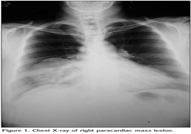

Hemostasis, closure of the post sites and using the anterior utility port as a site for chest tube drainage (Figure 4). Postoperative course was smooth with removal of the tube on the 2nd postoperative day and patient discharge home on the 5th day (Figure 5). Routine follow up visits showed nicely healed wound and no recurrence detected on 1 year follow up (Figure 6).

Figure 4